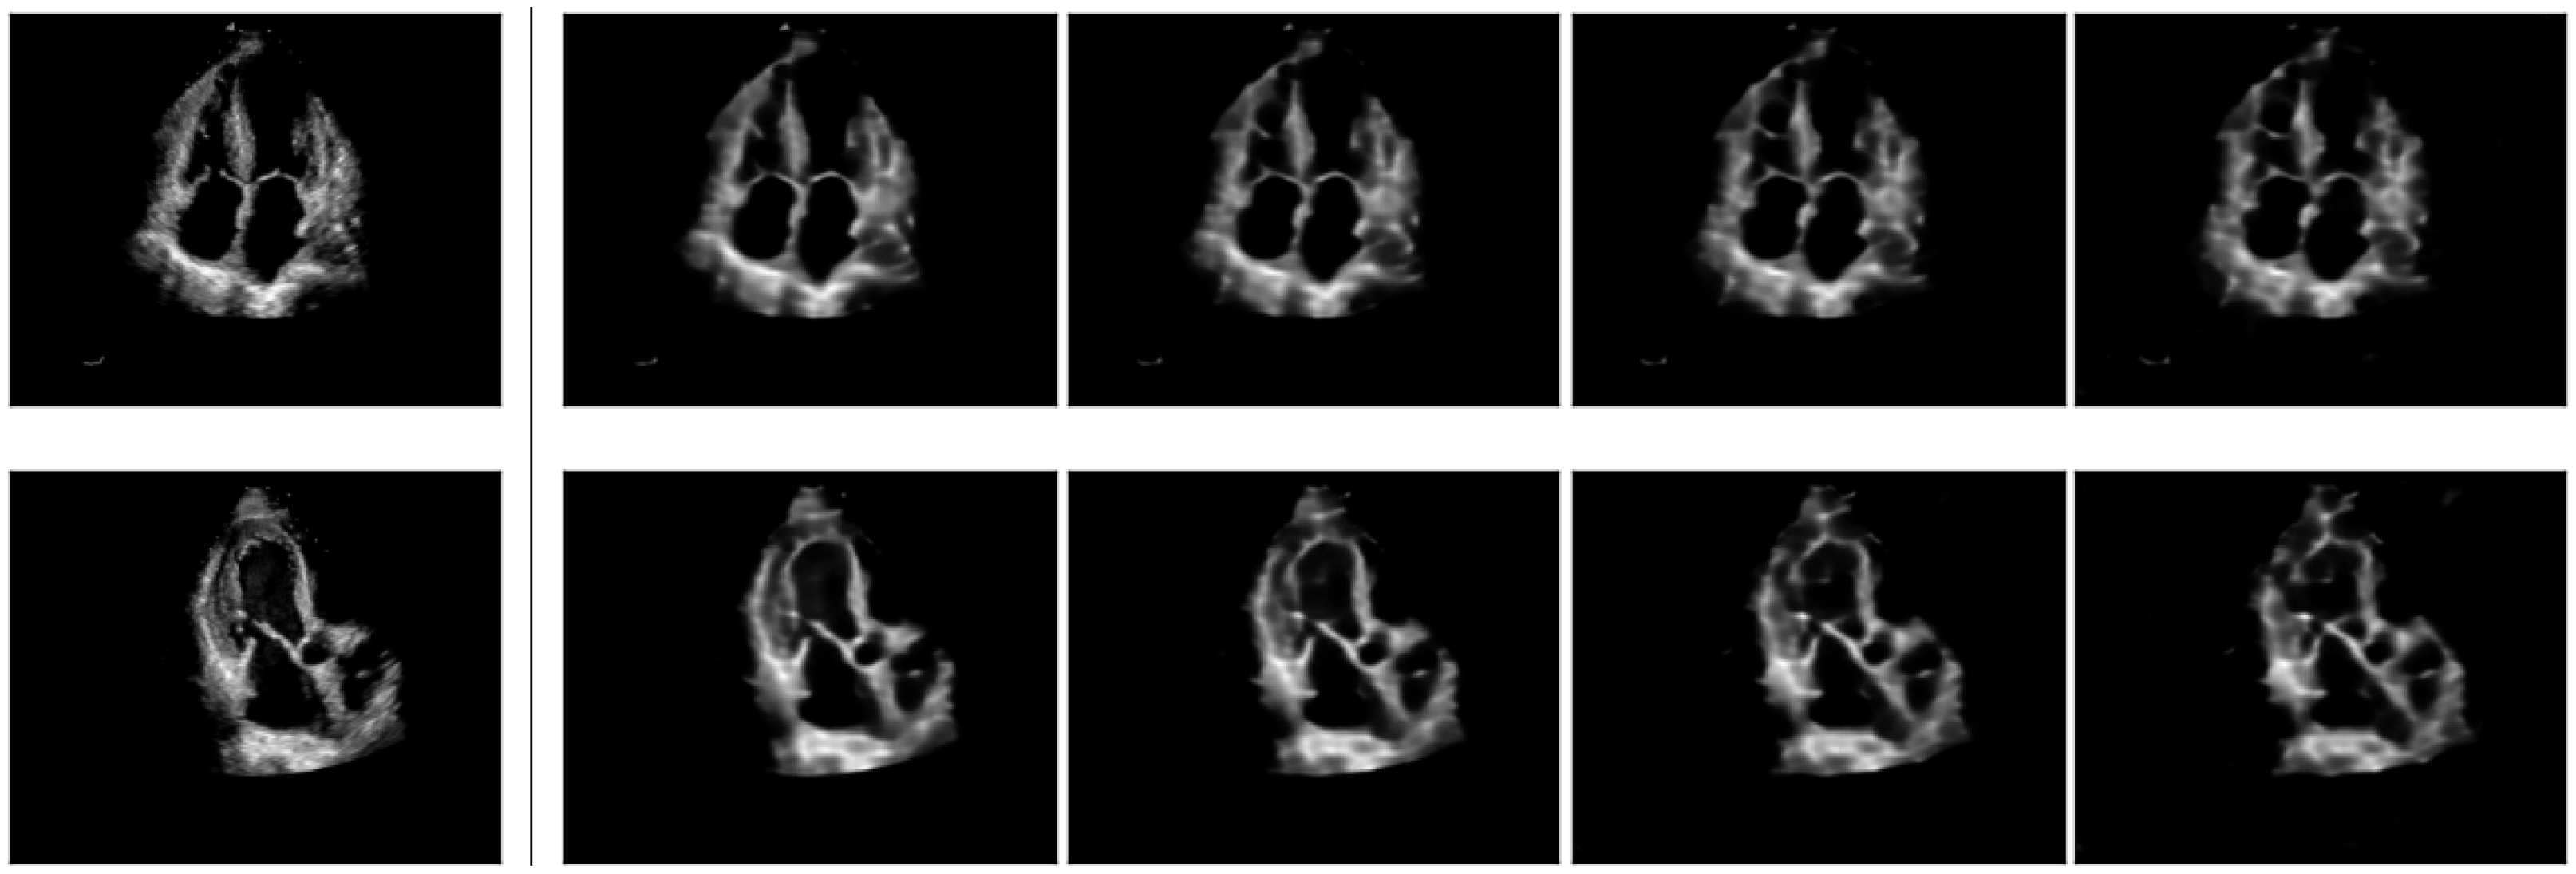

5.5. Style-Based Synthetic Data Generation

We further explore how style information can be used to generate synthetic data. Such data can be valuable for creating inputs conditioned by patient attributes, such as generating images with more textured walls. To achieve this, we leverage the known range of (since the constraint is enforced during training), and investigate style-based image generation. This involves adding Gaussian noise at various levels as described in Equation (7):

where controls the amount of noise injected into .

We then reconstruct the image using these style attributes. Randomly sampled reconstructions w.r.t. multiple (reusing the same sampled n) are illustrated in Figure 7, while Figure 8 illustrates reconstructions with multiple noise samplings and fixed . We observe that even with relatively high values, the reconstructions closely resemble the unaltered concepts, while the image textures are modified (with minimal changes to anatomical structures in terms of their shape or placement). This leads to the following observations:

- The model uses to decode semantic content, such as anatomical structures like chamber walls, blood pools, and valves, while is used to particularize local textures, shadows and speckles.

- With ConceptVAE, synthetic data can be generated by modifying only textures and speckles while retaining anatomical structures. This allows for the generation of novel samples that can serve as style augmentations without modifying the content, potentially enhancing the training performance of dense downstream models, such as those used for segmentation.

Figure 7.

Original images (left) displayed alongside reconstructions using with increasing levels of injected noise, . From the second column to the right, values are 0 (unaltered reconstruction), , and , respectively.

Figure 8.

Reconstructed images with unaltered (left) alongside three reconstructions with constant noise level . Each noisy reconstruction uses different noise, , as described in Equation (7).

The samples generated with ConceptVAE remain within the original data distribution, and thus can serve as a more calibrated augmentation method. In contrast, classical transformations such as rotations and blurring may generate data points with appearances not observed in the initial distribution (e.g., unnatural rotations or texture changes). Ultrasound medical imaging inherently introduces noise in video acquisitions in the form of pixel speckles. ConceptVAE simulates the effect of different realizations of echocardiography-specific noise, producing images that reflect this variability. Given the large variability between acquisitions and patients in ultrasound imaging [49], the proposed method can potentially improve the robustness of the models on downstream tasks.